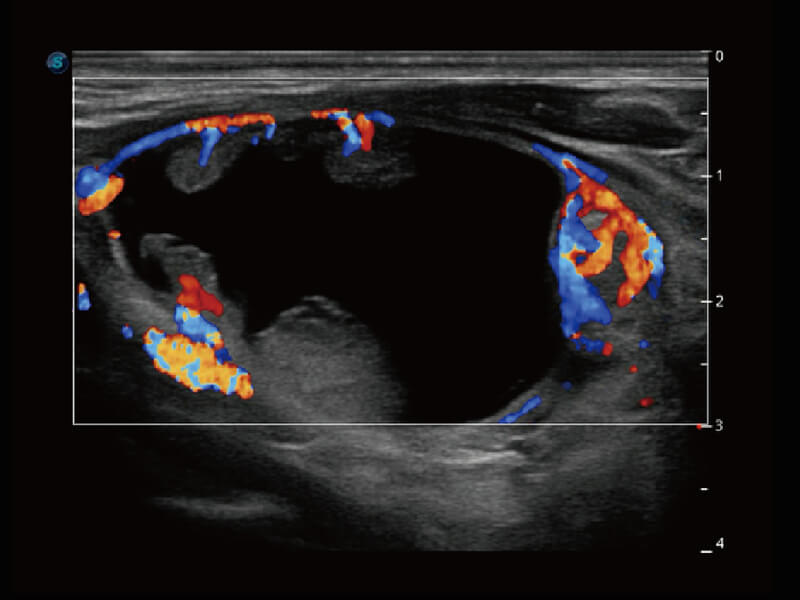

成像功能

性能优异的硬件架构,极大提升超声系统的运行效率和数据处理能力。相比以往超声成像系统,Wis+平台为您带来极快的响应速度和成像帧频,提升检查流畅度。

S60探头工艺,从前端信号处理每一个环节采集无损声学数据,真实还原组织原貌,再现解剖细节。